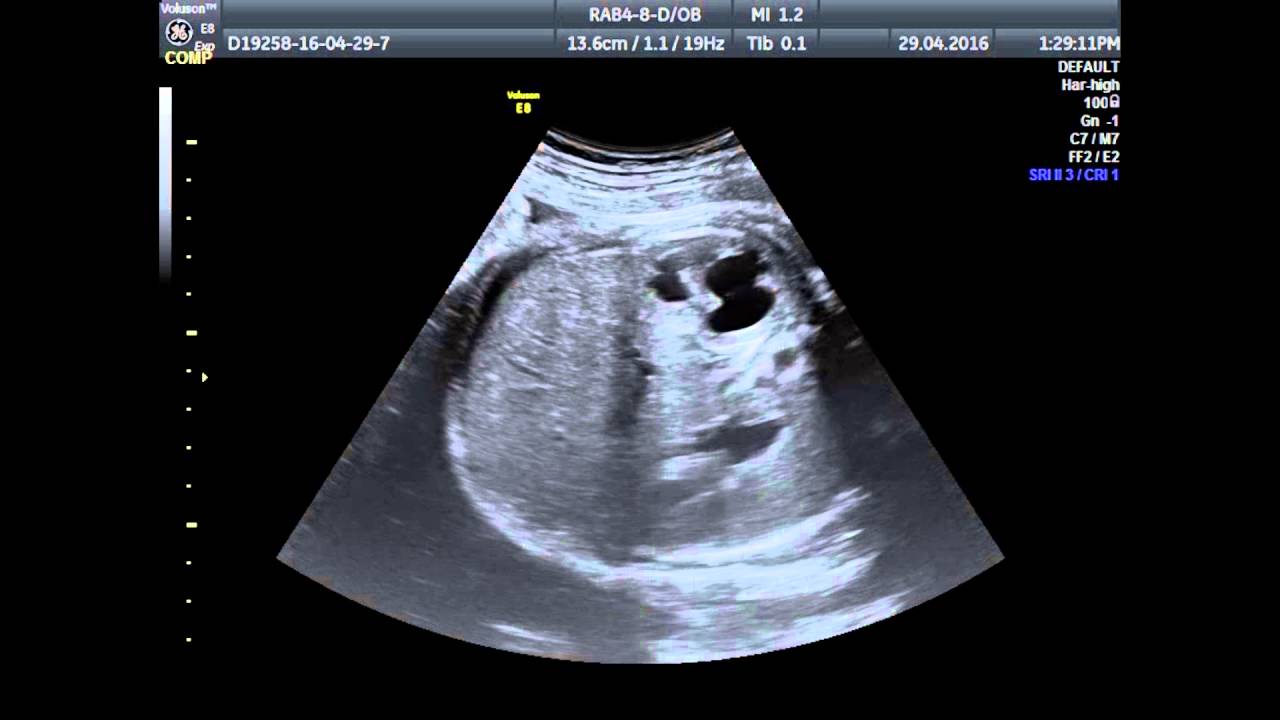

Как диагностируется

Самым точным и информативным методом диагностики гидронефроза является ультразвуковое исследование плода, который назначается для оценки параметров развития и выявления ранних патологий:

- УЗИ-диагностика позволяет оценить размеры органов, их соответствие стадии развития, функциональные характеристики, наличие признаков воспаления, новообразований и посторонних элементов.